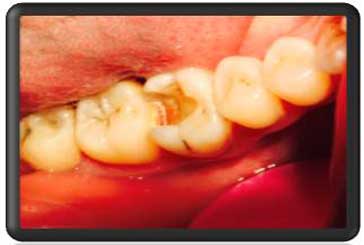

پوسیدگی ها کامل حذف شدند |

بدلیل نزدیکی به عصب ماده ای که نقش عایق دارد در کف حفره گذاشته شد. این ماده ساخت کمپانی اولترادنت آمریکاست |